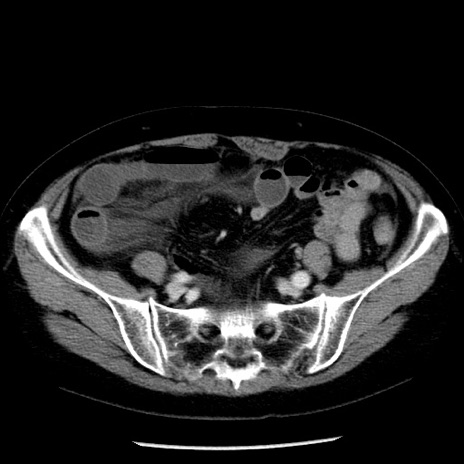

症例13(横断像)

【症例】70歳代女性

【主訴】腹痛、嘔吐

【現病歴】15時間程前(昨晩)より腹痛あり。今朝になっても症状の改善なく、嘔吐あり。腹痛も増悪あり、救急外来受診。

【既往歴】子宮癌全摘術後

【身体所見】意識清明、BP 121/72mmHg、P 74bpm、SpO2 100%(RA)、腹部:平坦・軟、腸雑音ほぼ聴取せず。下腹部・心窩部・臍左上に圧痛あり。反跳痛なし。

【データ】WBC 10600、CRP 0.15